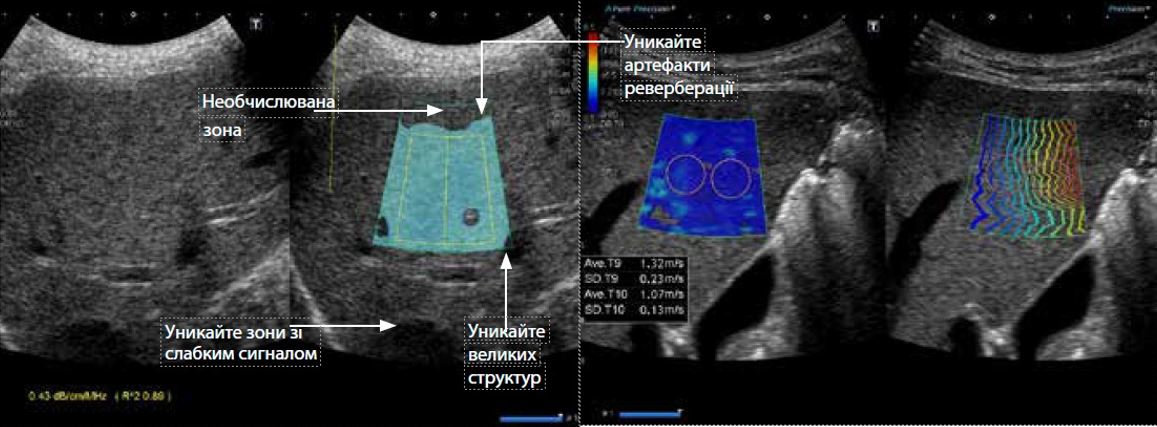

Малюнок 3 Нормальна печінка. Під час вимірювання АТІ важливо уникати ненадійних ділянок. Вимірювання АТІ та САР для нормальної печінки демонструє рівномірне згасання УЗ проміню.

Співвідношення між ATI і найсучаснішими методиками для оцінки стеатозу печінки

Були проведені клінічні оцінки для порівняння ATI з контрольованим параметром ослаблення (CAP, FibroScan®). На малюнку 3 показаний випадок з нормальною печінкою. CAP і ATI продемонстрували послідовну оцінку затухання. Щоб отримати надійні вимірювання ATI, важливо уникати ділянок з артефактами реверберації, великими структурами або ослабленими сигналами.